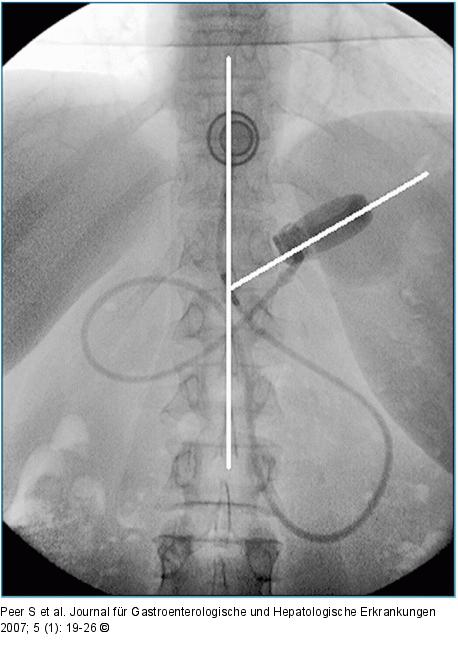

Abbildung 2: LAGB Normalbefund nach LAGB: Das Band bildet mit der Längsachse der Wirbelsäule einen Winkel von knapp 50° (Normalwert von 5–60°). |

Normalbefund nach LAGB: Das Band bildet mit der Längsachse der Wirbelsäule einen Winkel von knapp 50° (Normalwert von 5–60°). |